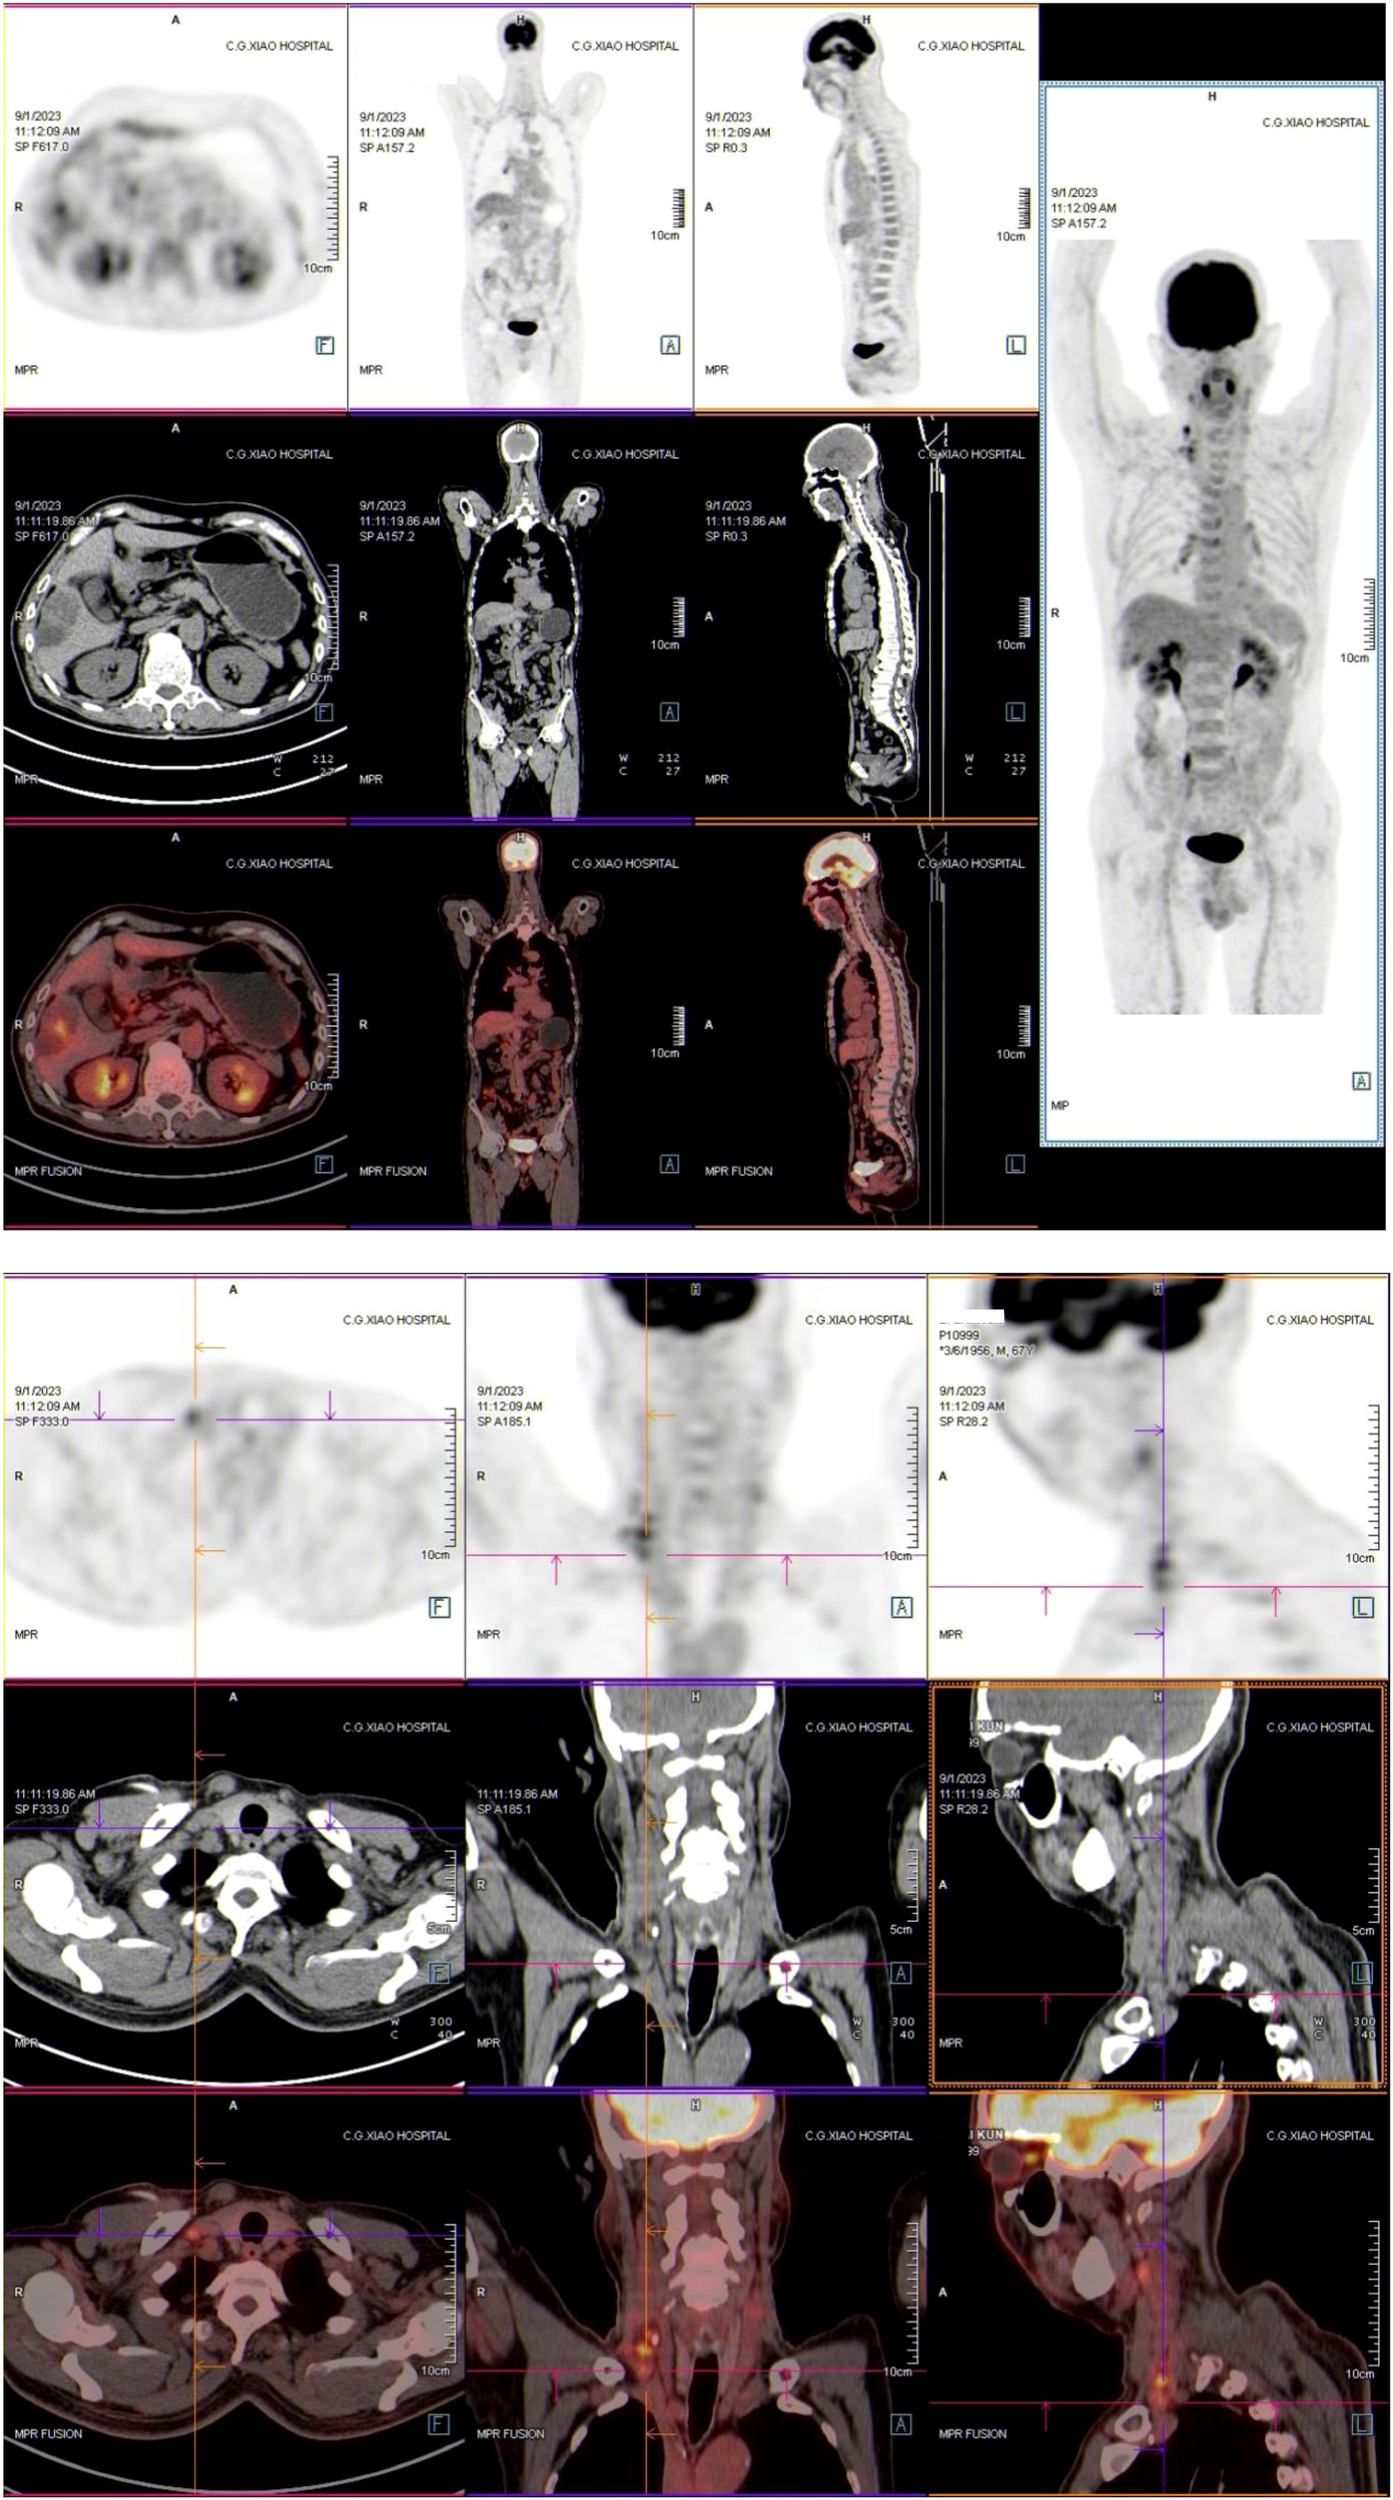

The first stage of ALPPS was performed in September 2023, consisting of cholecystectomy, right portal vein ligation, and right liver parenchymal division. Full body PET-CT images of the patient were shown in Figure 3. On day 37 post-surgery, reassessment showed improved liver function, with an ICG R15 of 5.8% and residual liver volume of 55.14% (Figure 2B). In October 2023, the second stage involved right hepatectomy and lymph node dissection. Pathological analysis confirmed moderately differentiated ICC with a tumor size of 65 mm × 60 mm × 40 mm, >80% tumor necrosis, and negative margins. No metastatic carcinoma was detected in the lymph nodes. The patient recovered well and was discharged. At 12 months post-surgery, no recurrence or distant metastasis was observed. The CT scan images were shown in Figure 4.

Figure 3

Full body PET-CT images of the patients in September 2023.